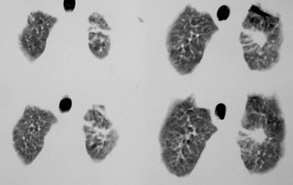

以下是引用sdqzwyx在2005-11-7 19:59:00的发言:[br]双肺弥漫大小不等的粟粒状结节影;肺纹理走行失去自然,粗细不均,边缘不规则,小叶间隔增厚;左上肺示不规则形致密影,从斑块边缘向周围伸出长短不一的致密索条影,临近的血管、支气管和叶间胸膜等结构受牵拉移位;左下肺示不规则团块状影,其内示空洞,洞内壁尚光整,左侧胸腔积液。右肺下叶背段亦示部分病灶融合。双肺可见局限性肺气肿。[br]诊断:结合病史符合三期矽肺表现(少数矽肺纤维斑块内可以形成空洞,一般认为是斑块中央感染引起坏死所致)但尘肺病人易合并肺结核,诊断可为三期+tb。所以此病人应进一步检查是否合并结核。